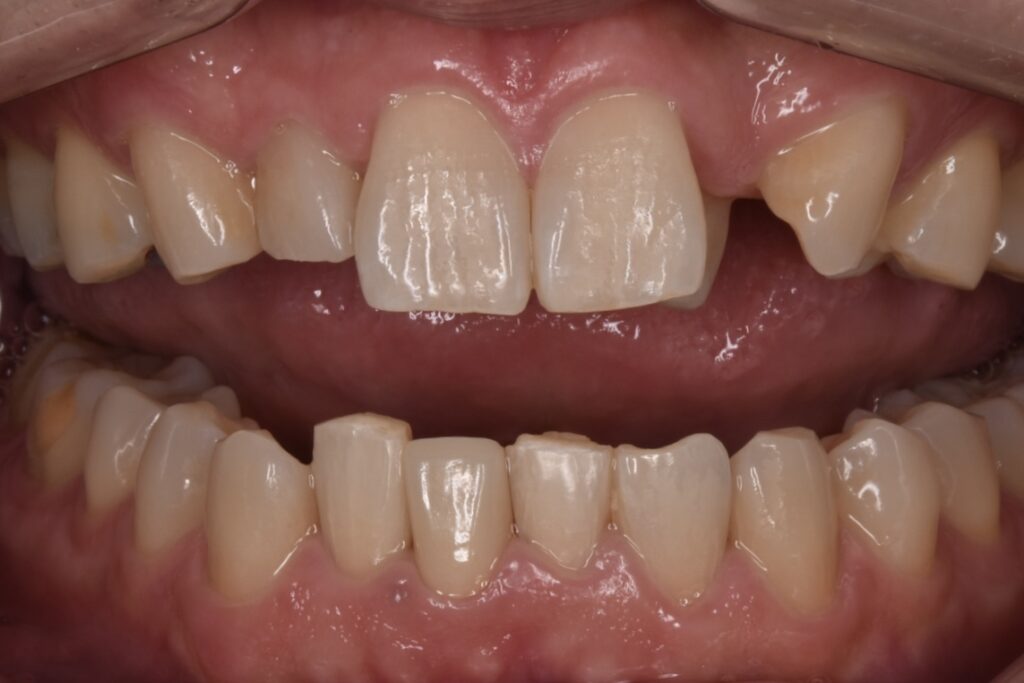

50代男性 下の前歯が東京の歯科で一年ほど前に作られた差し歯で、今回はそれが取れてしまったとご相談いただきました。検査の結果、歯が土台ごと折れていました。折れている場所が歯茎の中の方で折れていて、歯槽骨ギリギリの場所です。

歯が折れてしまっている現状では、このままセラミックをやりかえても予後が悪く長持ちしない点をお伝えしました。そこでご自身の歯を上に引っ張り出して骨からの距離を出してからセラミックで修復する意図的挺出(いとてきていしゅつ)をご提案させて頂きました。

さくらジルコニアプランでのジルコニアセラミックです。歯の色はA3というシェードです。色見本が20色近くありますので、そちらから選択して頂きます。